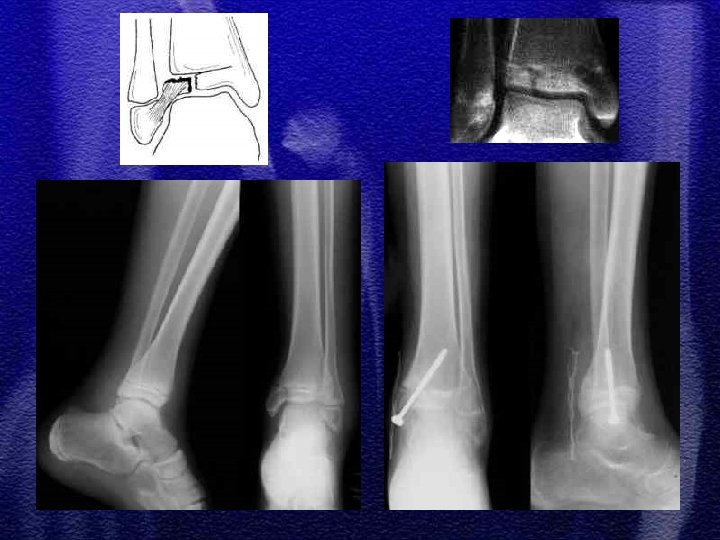

§ W zależności od mechanizmu urazu spotykamy różne typy złuszczeń od I do IV wg Saltera-Harrisa § Złuszczenia typu I i II leczenie zachowawcze gips - 4 tyg. § Złuszczenie typu III i IV leczenie operacyjne - śruby, druty Kirschnera § Złuszczenia wielopłaszczyznowe typ II i III występujące jednocześnie w nasadzie dalszej kości piszczelowej